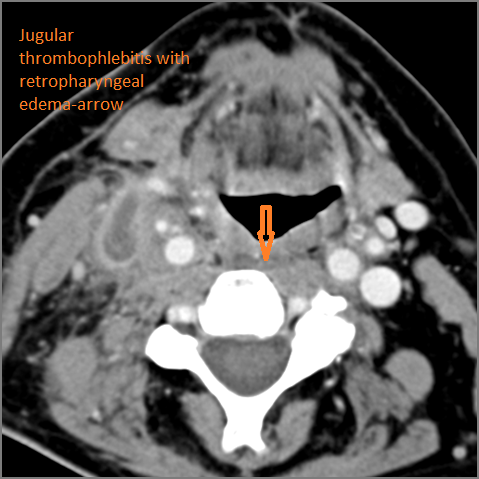

There is abscess within the adjacent deep neck, retropharyngeal and/or prevertebral spaces.

Vascular Findings